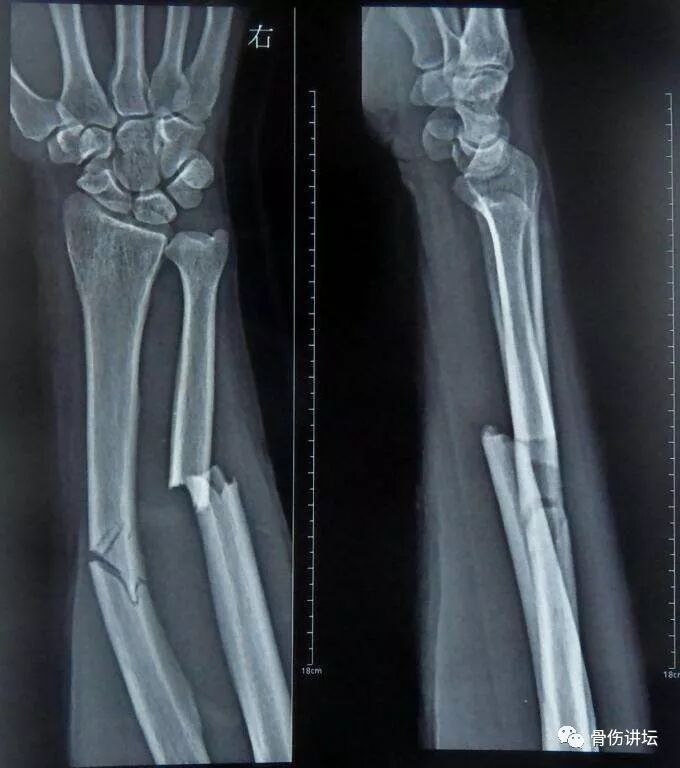

桡骨远端骨折 内固定 外固定手术技巧 关节 克氏针 肱桡肌 网易订阅